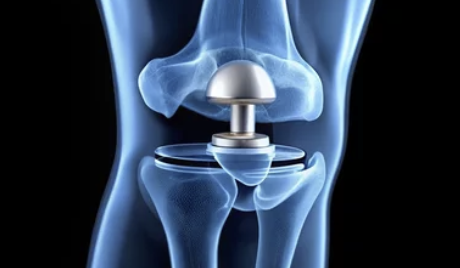

무릎 인공관절 수술은 손상된 무릎 관절을 제거하고, 이를 대신할 인공관절을 삽입하는 수술입니다. 주로 퇴행성 관절염, 연골 손상, 또는 무릎 관절의 기형으로 인해 무릎 기능이 심각하게 손상된 사람들에게 시행됩니다.

2. 인공관절의 종류

- 국산 인공관절과 수입 인공관절의 가격 차이가 큽니다. 수입 제품은 품질과 기술력이 우수할 수 있지만 가격이 더 비싸며, 국산 제품은 상대적으로 저렴하지만 품질도 우수한 편입니다.

3. 수술 방식

- 부분 인공관절 수술과 전체 인공관절 수술에 따라 비용이 다릅니다. 부분 인공관절 수술은 무릎의 일부만 교체하는 방법으로, 비용이 상대적으로 저렴할 수 있습니다. 반면에 전체 인공관절 수술은 무릎 전체를 교체하는 방법으로, 더 복잡하고 비용이 높습니다.